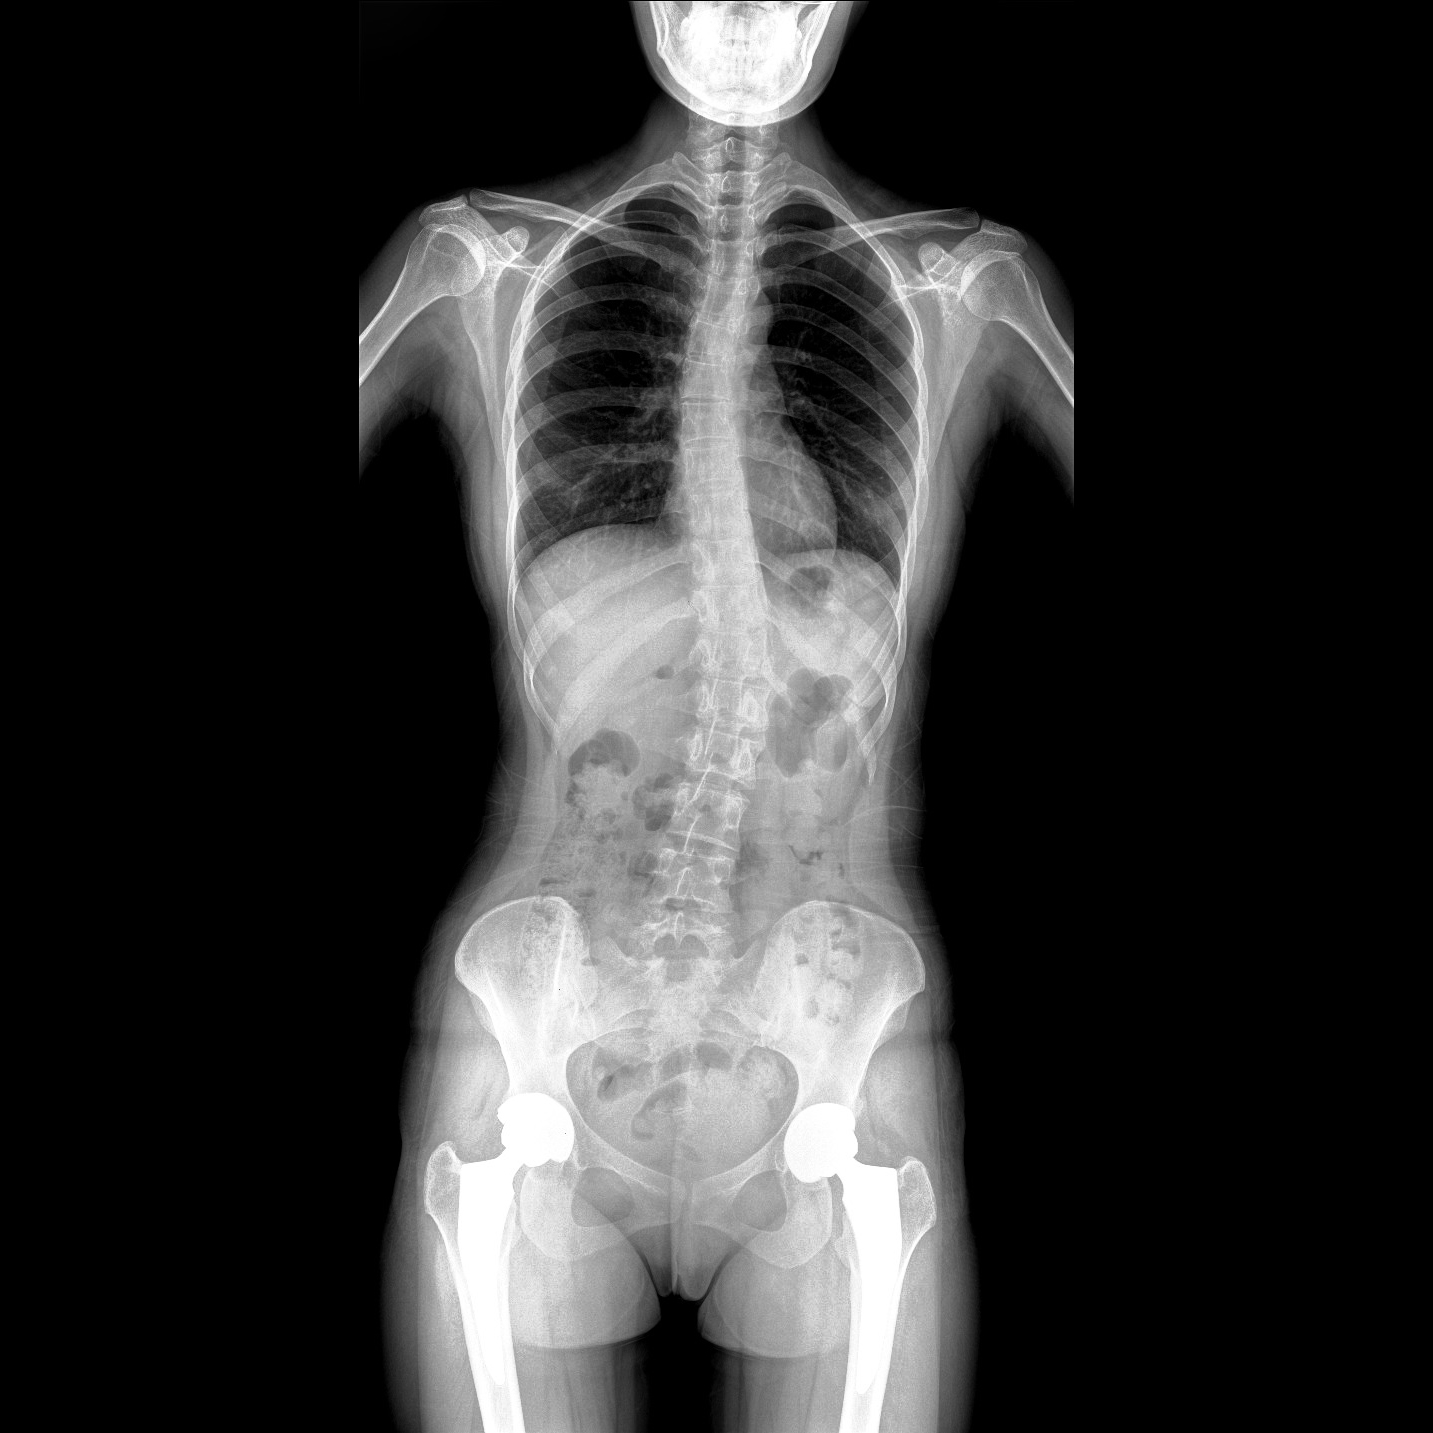

支持全脊柱攝影、雙下肢攝影、脊髓造影、復雜創(chuàng)傷、人工關節(jié)置換、關節(jié)損傷的修復重建等大視野臨床應用

17"*34"有效視野,一次成像不拼接。相較于多張攝影再軟件拼接的DR設備,PLX8600解決了拼接圖像存在密度不均勻,拼接處圖像配準和放大效應等問題,給臨床帶來了大視野影像解決方案,可一次性覆蓋全脊柱或雙下肢影像。

除常規(guī)靜態(tài)攝影外,PLX8600大平板具備動態(tài)透視和點片功能,透視采集功能可支持大視野、多角度的可視化觀察。通過可視化的動態(tài)影像,配合點片功能,能夠很好的觀察復雜部位病灶,有效的抓取關鍵幀,降低患者多次攝片的概率。如:全脊柱狀態(tài)評估、長骨關節(jié)活動度、下肢靜脈造影瓣膜功能評估、消化道功能評估、脊髓造影等更多大視野臨床應用。